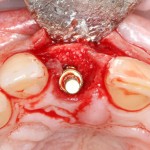

После удаления зуба и сопутствующей гранулемы, остается большая по размеру лунка с тонкой и поврежденной воспалительным процессом вестибулярной стенкой:

Первым делом, необходимо определиться с подготовкой лунки под имплантат. Проверить правильность позиционирования лунки можно с помощью аналогов имплантов, входящих в комплект XiVE Dentsply Implants:

Напомню, что при правильном позиционировании импланта в области фронтальных зубов, он прилегает к небной стенке лунки, а его ось выходит на небную поверхность будущей коронки. В крайнем случае, на режущий край.

Имплантат по объему всегда меньше, чем сам зуб:

Поэтому у нас возникает вопрос заполнения «пустого» пространства между вестибулярной стенкой лунки и поверхностью импланта. И, как ни странно, с Bio-Oss Collagen это удобнее сделать до установки имплантата.

Графт адаптируется (с помощью скальпеля), устанавливается в нужное положение. Для этого, опять же, очень удобно использовать аналоги имплантов из имплантологического набора (в крайнем случае, остеотомы или пины параллельности):

Напомню, нет необходимости заполнять графтом всю лунку. Тем более — полость удаленной кисты или гранулемы. Поэтому 100 мг вполне хватает, чтобы аугментировать лунку любого объема.

Благодаря своим свойствам. Bio-Oss Collagen не забивается в подготовленную лунку импланта, не съезжает и не сползает при его установке:

Вот, собственно, и всё. Далее, наш биоматериал ведет себя совершенно также, как и обычный Bio-Oss — он быстро пропитывается кровью и отлично удерживается на месте: